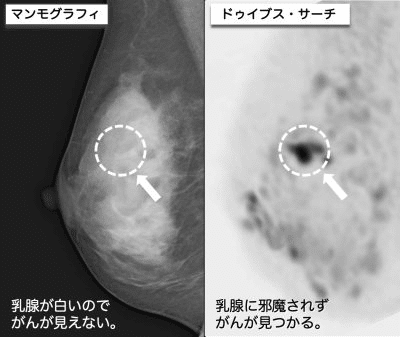

2つ目は、日本人に多いと言われる乳腺組織が多い高濃度乳房(デンスブレスト)の場合、がんが見えづらいという問題が解決していない点です。検出率が半分となるClass D(Class 4)の高濃度乳房は、最新のマンモ(トモシンセシス、3Dマンモ)でも解決できていません。また、ご自分が高濃度乳房かどうかを受診者が知らされないことも多いんです。

検診では、乳房を圧迫せず、着衣のまま検査を受けていただけます。検査は15分ほどで終わり、病院の滞在時間も1時間程度。X線を使用しないので被曝の心配がゼロで、造影剤も使わないため注射も不要です。また、マンモグラフィーで乳がんが見つかりにくい高濃度乳房での検出率も高いため、高濃度乳房で不安を抱えている方にもおすすめしたい検査法と言えます。

痛みや恥ずかしさのない乳がん検診(世界初)。ドゥイブス(DWIBS)法®というMRI技術を用いる。乳房を圧迫せず着衣のまま検査可能な乳がん検診で、短時間(15分)で終わり、病院に1時間寄るだけでOK。X線を使用しないので被曝がなく、造影剤も使わないため注射も不要。乳がんが見つかりにくい高濃度乳房での検出率も高い。全国29施設で受診可能(2021年9月現在)。